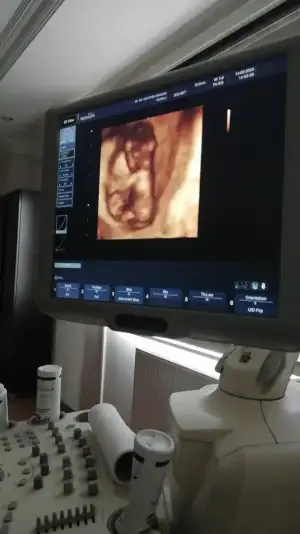

dr soylemeden siz gorun genital nub teorisi ( bebegin cinsiyeti)

Bacak arası nubuda dik görünüyor erkek 11+2 dimi usg 12+ yada 13 olursa paylaşın A Aryaam

Dr. umda çok düşük ihtimal ile kız olabilir diye tahmin etti. Ama netlik için çok çok erken 2 hafta sonra netleşir dedi.

Canım ben 11+ yada 12 + nublara bakıyorum 14+2 de nub degil organı gelişmiş oluyor 😊 hadi 13 de olabilir usg dr kız dediyse kızdır cnm 😊 hmm 12 de erkek dedi diyorsun. hayırlısı olsun 🙇